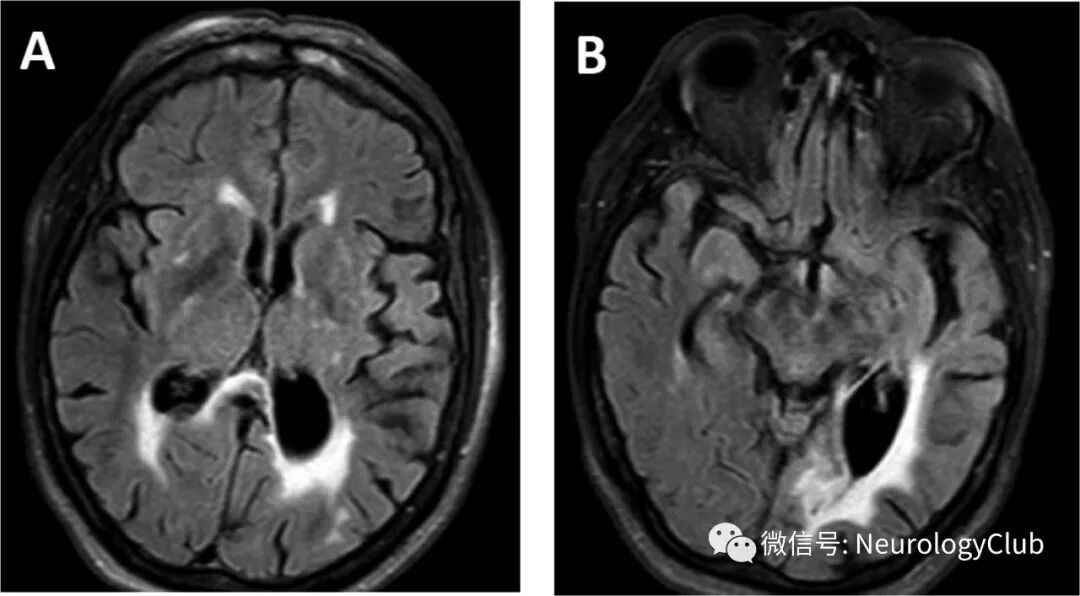

最初的头颅CT提示左枕叶陈旧性梗死。脑脊液提示白细胞25×10^9/L(100%淋巴细胞),蛋白升高至1.7g/L,糖3.9mmol/L。单纯带状疱疹病毒和水痘-带状疱疹病毒PCR阴性。入院后患者意识障碍加重,Glasgow昏迷量表评分7分,转至重症监护室。行头颅MRI提示广泛的皮质下水肿,累及白质传导束,深部灰质核团,脑干和小脑,伴少数局灶性微出血(图1)。

(图1:最初的FLAIR可见广泛的皮质下水肿,累及白质,基底节,内外囊和中脑)